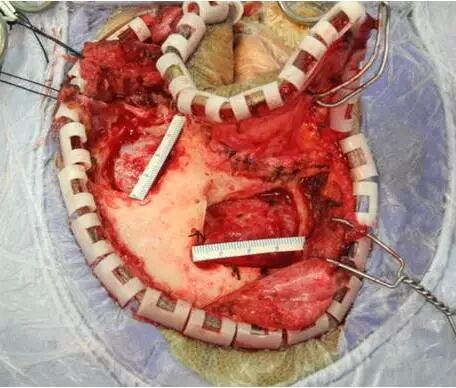

坐位听神经瘤切除术视频(摘自鲍教授上述讲课)

鲍遇海教授:坐位听神经瘤切除术